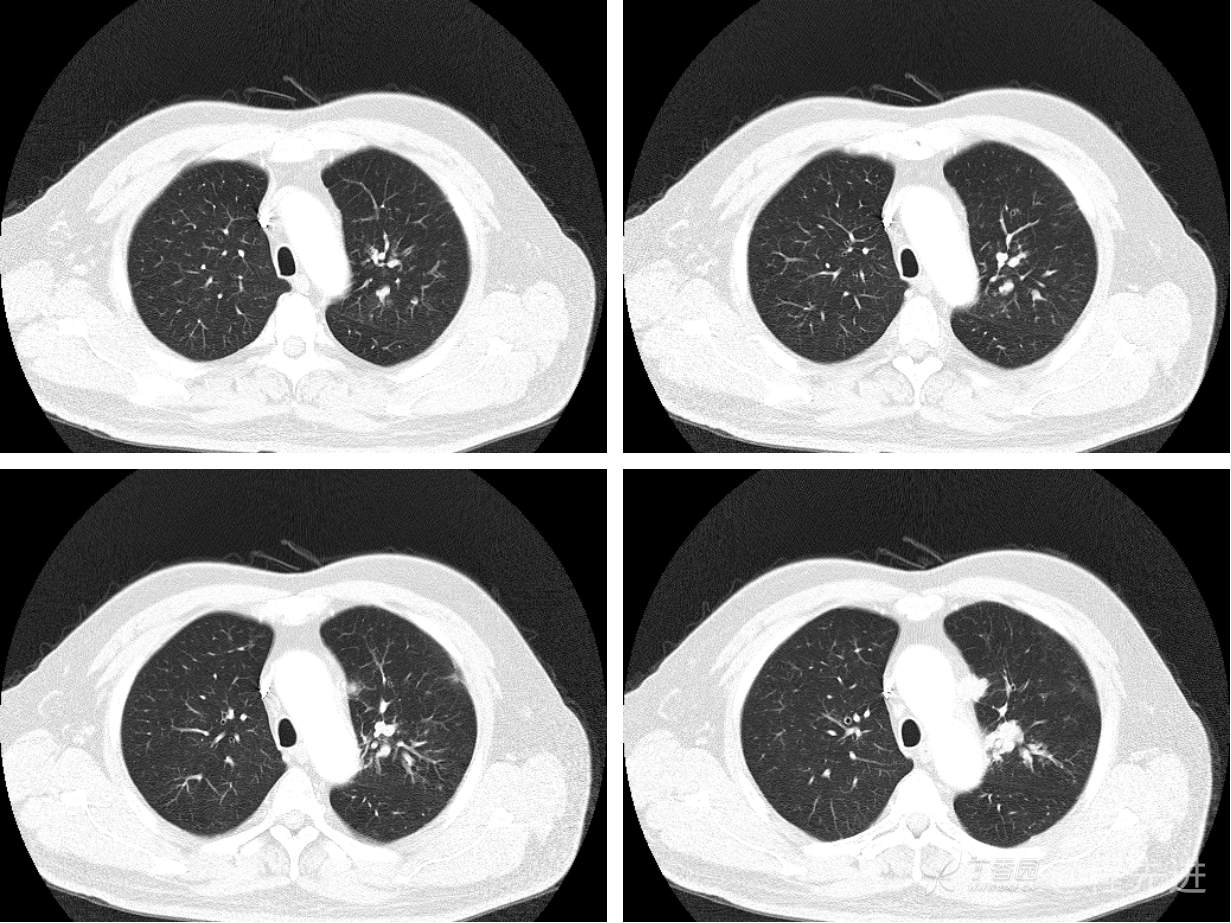

现病史概要:患者入院前约半月无明显诱因下出现咳嗽、胸闷症状,无明显发热症状,咳少量白痰,无明显咯血、喘息、头晕等不适,就诊我院查胸部CT示上纵膈肿物,左肺上叶支气管内肿物,现为行进一步治疗收入胸外科,患者近来饮食睡眠尚可,二便如常。